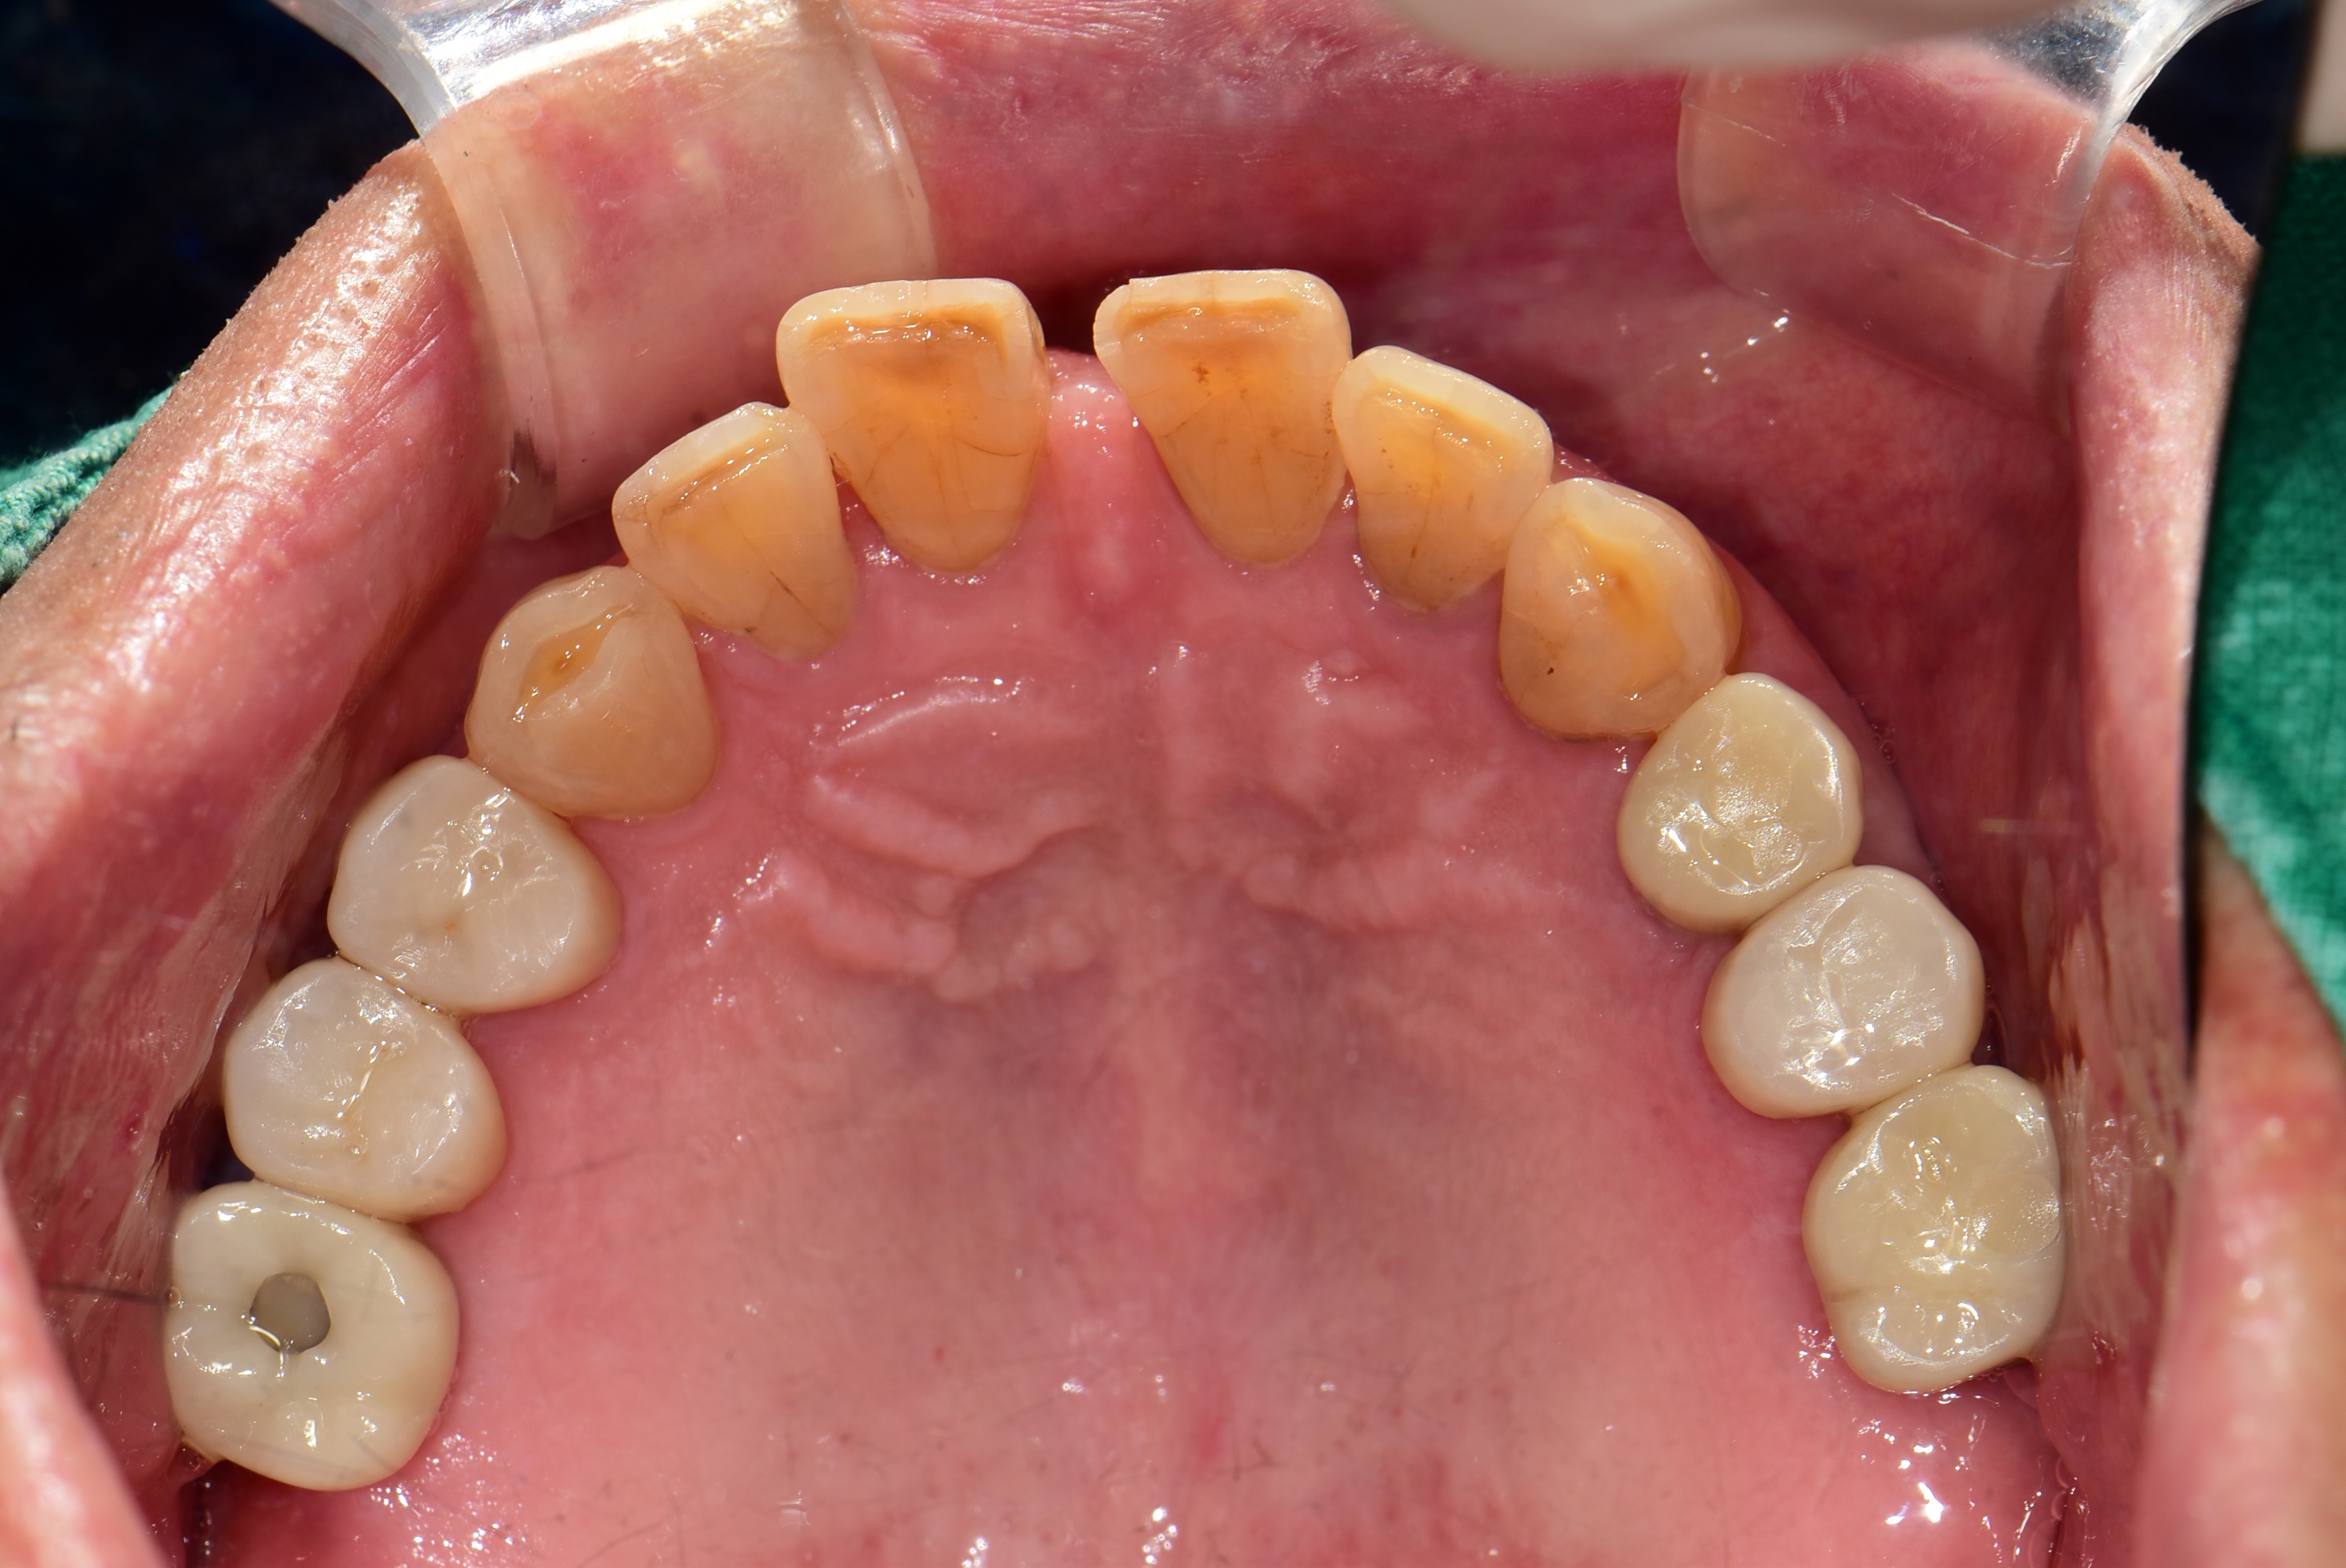

김포 서울케이치과에서 진행한 어금니 다수치아 임플란트 사례입니다.

심한 충치로 인하여 뿌리만 남은 어금니로 인하여 식사가 불편하셨던 50대 남성 환자분이 소개로 내원하셨습니다.

경제적인 이유로 첫번째 어금니까지만 임플란트를 식립하셨고, 6개의 작은 어금니는 심한 파절과 마모로 크라운 치료를 하였습니다.

<치료 전>